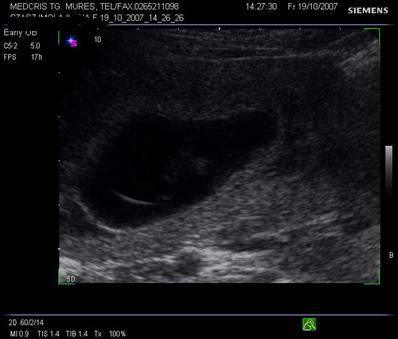

Fig. nr.205. Placenta fundica si posterioara ( normal inserata, cu sageata ) la o sarcina de 16 sapt.

Fig. nr. 208. Placenta gr O la 16 saptamani gestationale, cu sageata se remarca insertia centrala placentara , a cordonului ombilical

Fig. nr.209 Placenta gr. I la o sarcina de 23 saptamani gestationale ( sageata indica ondulatiile minime ale placii choriale )

Fig. nr.210. Placenta gr. II la o sarcina de 30 sapt. gestationale, sageata indica proeminenta ondulatiilor dinspre placa choriala , spre placa bazala

Fig. nr.211. Placenta grad. III la 41 saptamani gestationale, se remarca in structura placentara hiperecogenitati concentrice, in jurul unor zone relativ anecogene